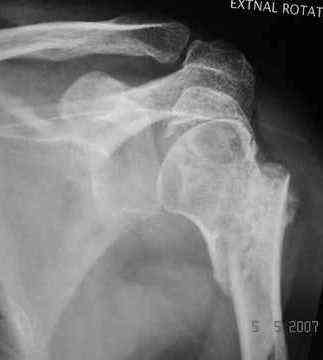

Dear all, A heavy built 30-year-old male patient sustained fracture dislocation of left shoulder about 8 months back.

For this ORIF with K-wires was done elsewhere. K-wires were removed at 6 weeks and patient advised physiotherapy. He has been doing physio dedicatedly since then.

He has 60* elevation…primarily it is scapulothoracic motion. External rotation at side is minus 30*.

Movements are painful.

Looking at his previous x-rays, I was thinking of refixing the greater tuberosity, however got anaxillary view done today which was never done during this period and this shows non-union.

It looks like the initial injury was a head splitting fracture. Presently the patient has a non-union at the level of the anatomical neck with displaced tuberosities. I would tackle the non-union, and would try to replace the tuberosities, a difficult procedure. I would use the proximal humerus locking plate from the AO.